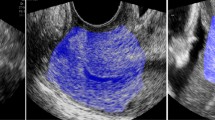

To investigate the relationship between cervical length (CL) at 37 to 40 weeks and delivery within 7 days and delivery by 41 weeks.

We performed transvaginal ultrasound to measure CL in women with singleton gestations at 37 to 40 weeks. We then used a receiver operating characteristic curve (ROC) to assess the relationship between CL and delivery within 7 days and delivery by 41 weeks.

For the 120 women included in the analysis, the mean CL (±s.d.) was 25.3±9.8 mm. The logistic regression model to predict each of the outcomes includes gestational age at ultrasound (GA-US) and CL. Neither birthweight, nor parity seems to affect the probability of delivery within 7 days. The ROC curve was used to assess the probability of spontaneous labor within 7 days at each CL measurement. The likelihood ratio of delivery within 7 days when CL is ⩽10 mm is 12.

CL measurement at 37–40 weeks is an independent predictor of delivery within 7 days and delivery by 41 weeks regardless of GA-US. This information can be utilized when counseling patients regarding the management of term pregnancies.